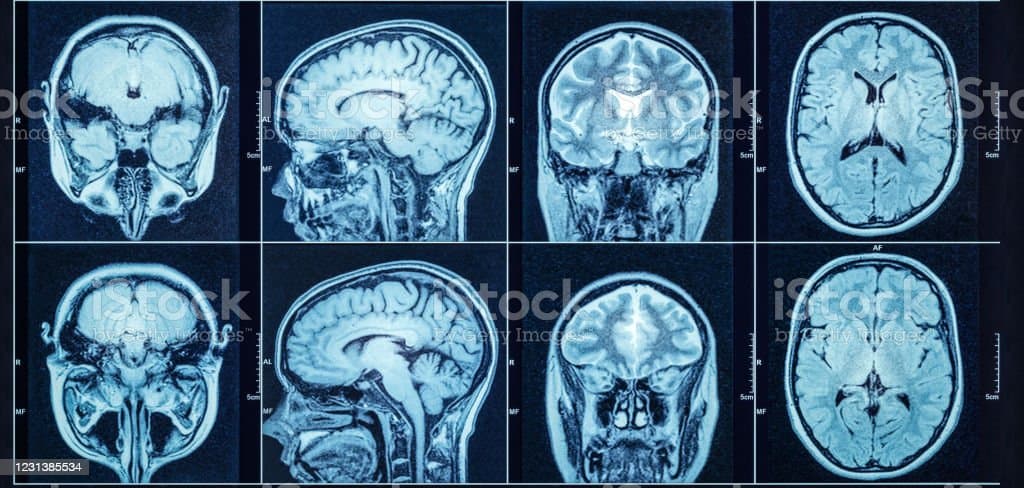

2. 뇌 영상 검사 : 뇌 영상 검사는 뇌 내부의 구조와 혈액 흐름을 평가하기 위해 사용됩니다. 주로 사용되는 뇌 영상 검사에는 컴퓨터 단층 촬영(CT 스캔), 자기 공명영상(MRI), 혈관조영술 등이 있습니다.